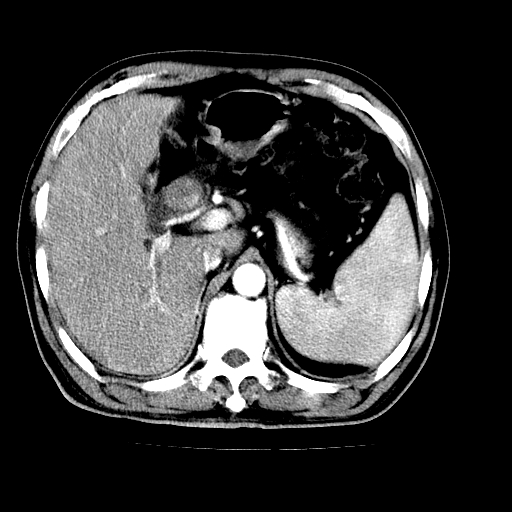

男,66岁,上腹部不适、黄染一周。彩超示:肝左叶占位,肝内胆管扩张,胆总管扩张,胆总管占位?

肝左叶不规则软组织肿块影,边缘不规整邻近肝实质受累分界不清;肝内胆管(左叶)明显扩张成“软藤状”,诊断:肝左叶胆管细胞癌。

左叶胆管细胞癌累及胆总管,门脉左支受侵,慢性胆囊炎胆结石,左肾小囊肿

支持肝左叶肝内胆管细胞癌伴胆总管及门脉左支受侵。

胆囊缩小,其内胆汁浓缩,也提示梗阻部位应该位于胆囊管起始部以上或是胆囊管受累及,支持肝外胆管癌。